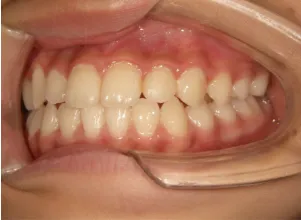

治療中➁小3:9y8m QH、BH、前歯並び替え終了

モノブロック装置(筋機能的咬合誘導装置)スタート